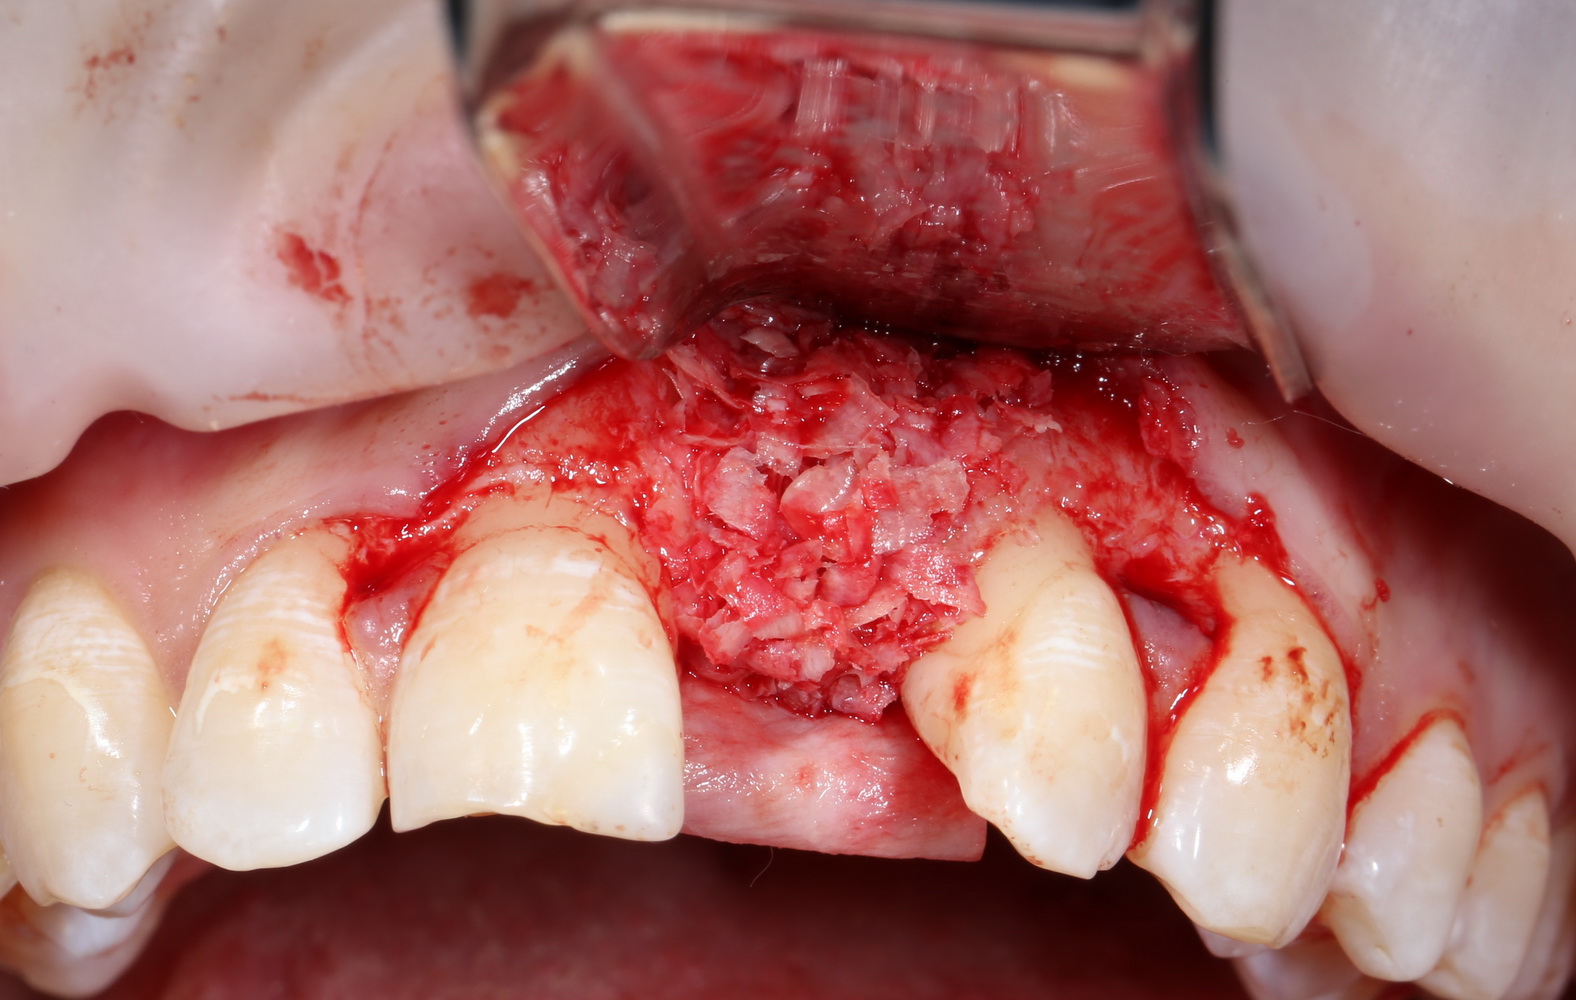

Имплантация и остеопластика (наращивание костной ткани): вместе или врозь? Часть I.